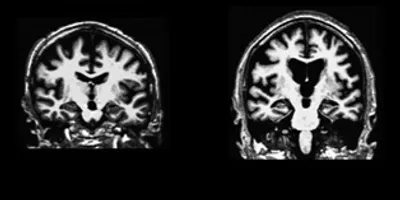

Sleep Loss and Brain Aging

Customary is NOT the same optimal when it comes to sleep. Specifically, let’s talk about a commonly repeated disclaimer, “No, I don’t sleep so well, but, hey, people always sleep less as they get older.” The defense is repeated for good reason as it does seem to be true – the quality and duration of sleep both decline in many if not most people with aging, starting even in your 40’s, which to me sounds still very young!